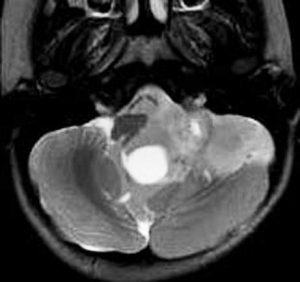

第4脳室床に発生した典型的な上衣腫 EPN-PFA の画像です。水頭症になって,頭痛と嘔吐,意識障害で発症しました。典型的なMRI画像と病理所見です。MRIでは第4脳室からマジャンディー孔を越えて脊髄背側まで長く腫瘍が伸びています。腫瘍内部に小さなのう胞が複数みられます。病理像では,血管周囲に細胞核がない無核野が認められます。血管周囲に伸びた繊細な単極性突起が集まった領域です。これは,血管周囲偽ロゼット perivascular pseudorosette という上衣腫に特徴的な病理所見です。

幼児の巨大な上衣腫です。左ルシュカ孔から延髄を取り囲む様に小脳延髄角槽に進展しています。最も典型的で治療が難しいタイプです。これはT2強調画像ですが,ガドリニウム増強されないものでした。

左が術前,右が術後です。脳底動脈の周囲が摘出できませんでした。幼児ですが手術後には局所照射をするしか方法がありません。